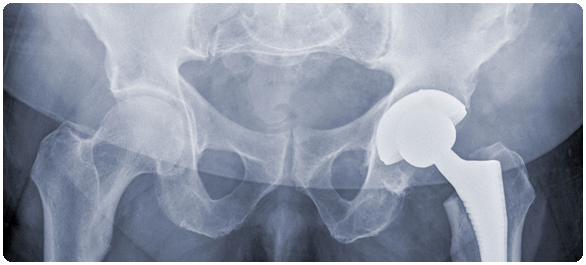

สะโพกหัก (Hip fracture) ถือเป็นการบาดเจ็บที่รุนแรงชนิดหนึ่ง เพราะสามารถทำให้เกิดโรคแทรกซ้อนจนเสียชีวิตได้ ความเสี่ยงของสะโพกหักจะเพิ่มขึ้นตามอายุที่มากขึ้น เพราะผู้สูงอายุมักมีกระดูกไม่แข็งแรง เป็นโรคกระดูกพรุน (Osteoporosis) นอกจากนี้การที่กินยาหลายชนิด สายตาที่แย่ลง และปัญหาเรื่องการทรงตัว ก็ยิ่งเพิ่มโอกาสในการหกล้ม ทำให้กระดูกหักได้